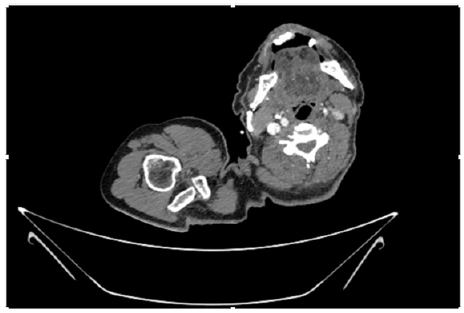

55-years-old chronic smoker had acute, severe pain in the right upper limb for one week; it was cold upto mid arm with skin discoloration. He also noticed numbness and weakness of movement of elbow joint. He underwent below elbow amputation in February 2023 for acute ischemia of left upper limb. He was a current chronic smoker; 15 pack year. General condition was weak; temperature was normal; blood pressure was 100/60mmHg; heart rate was 92/minutes with sinus rhythm; SpO2 was 97% on air; heart was normal. In lower extremities, all peripheral pulses were intact. Local Examination of right upper limb revealed as follows: tenderness; coldness; discoloration; decreased motor function and sensory modalities. Axillary, brachial and radial pulses were not palpable. Hand-held Doppler failed to detect any signal in arterial system; therefore, we arranged for emergency embolectomy. complete occlusion of right upper limb arterial system Full blood count showed high hemoglobin (14.6gm%); normal total WBC and platelet count. Coagulation profile was normal. Parenteral unfractionated heparin, antibiotics, tramadol, proton-pump inhibitors, anti-platelets and HMG CoA reductase inhibitors were given. Doppler ultrasound demonstrated complete occlusion of right upper limb arterial system. CT Angiogram illustrated occlusion of subclavian artery downwards on both sides. Figures 1-14 shows complete occlusion of right subclavian artery without collaterals. On Day ‘2’ of admission, the patient passed black tarry stool for 3 times. However, the vital signs were stable; blood pressure was 100/60mmHg; heart rate was 92/min; SpO2 was 97% on air; the abdomen was soft and not tender. Above elbow amputation was done on Day ‘2’ of admission. Intra-operative findings were as follows: (1) no active bleeding at brachial artery; (2) thrombosis along brachial artery; (3) muscle color and consistency were not healthy.

Figure 10: CT Angiogram at upper arm showing totally occluded right axillary artery; normal internal carotid artery and external carotid artery.